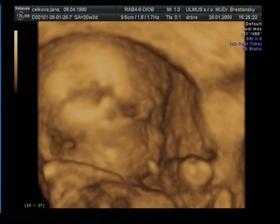

Nase prve male potesenie Martinko a ako rastie